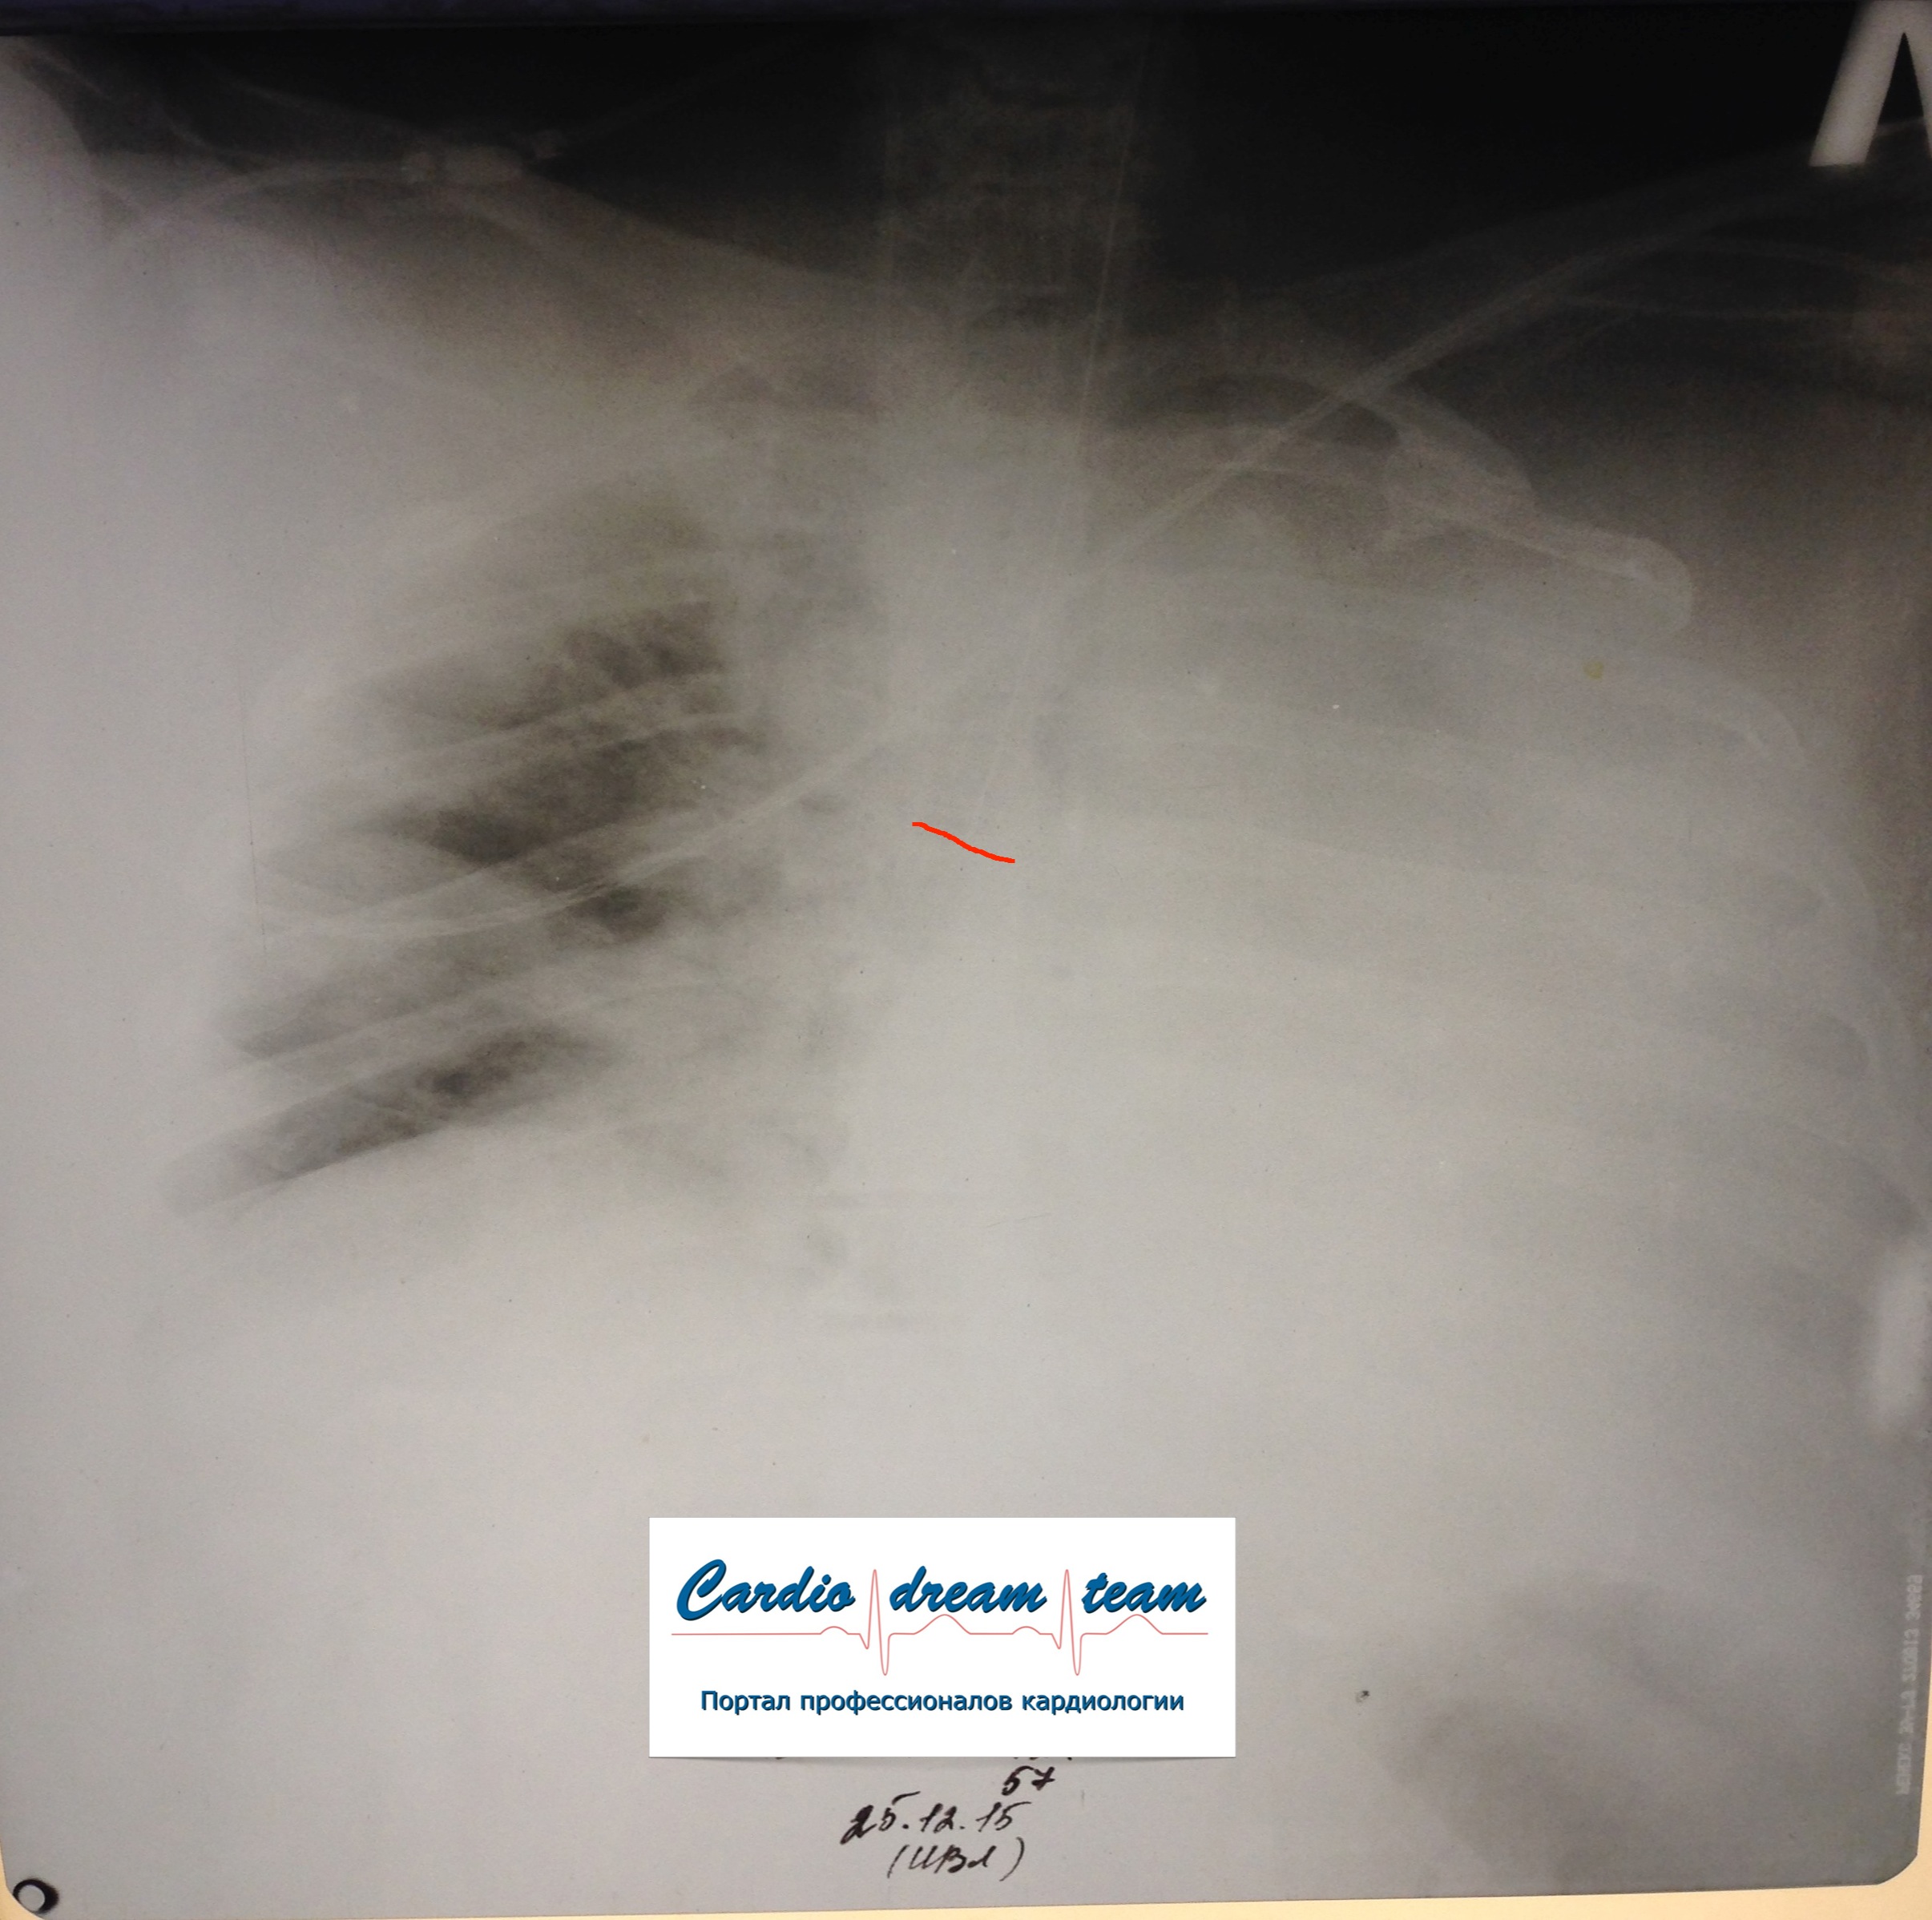

Гиповентиляция правого легкого потому, что интубационная трубка в правом легком. Конец трубки указан красным.

Не обсуждалось